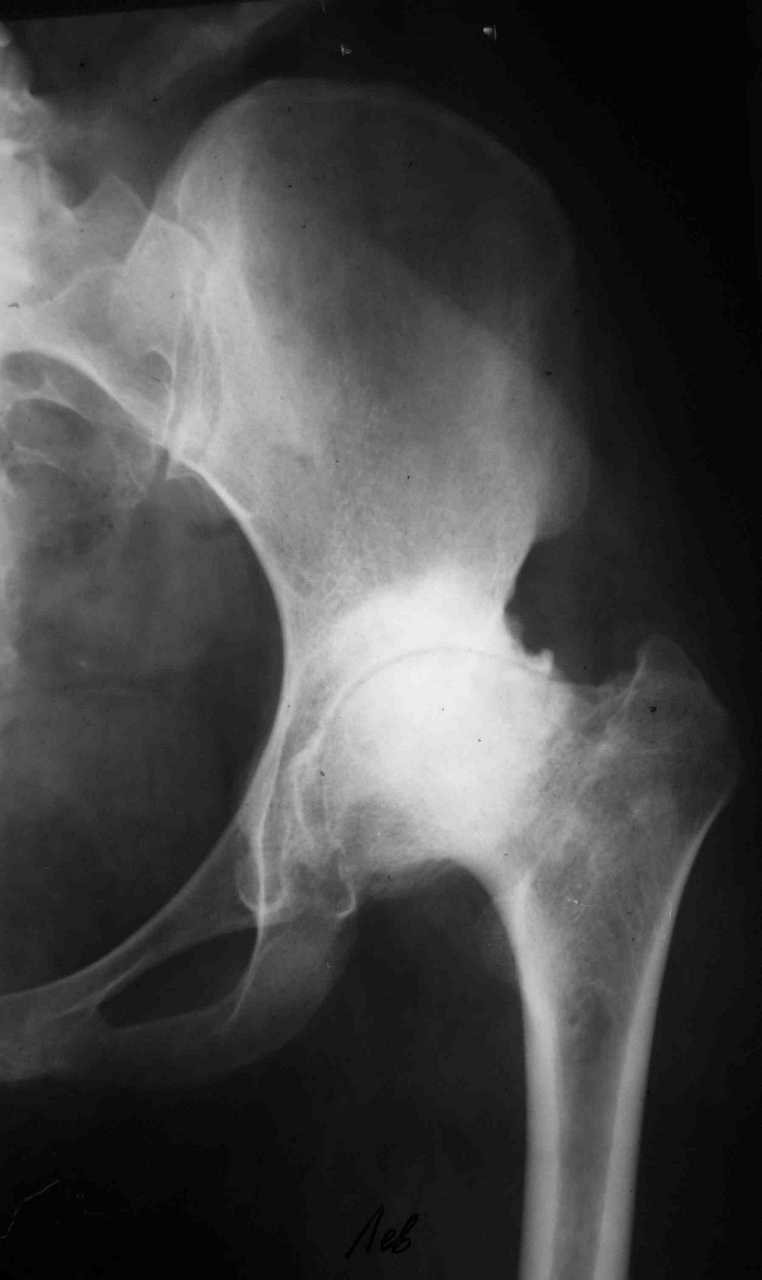

Уважаемые коллеги! К мне обратилась моя бывшая пациентка, 22 лет, с просьбой об эндопротезировнии коленного сустава. От артродеза категорически отказывается.DS: Врождённая аномалия развития левой нижней конечности. Состояние после удлинения бедра и голени (около 45 см). Варусная деформация шейки лев. бедра. Лев. коксартроз II ст. Лев. гонартроз III ст. Разгибательная контрактура лев. коленного сустава. Парез малоберцового нерва слева. Укорочение лев. н/конечности 1,5 см. Жалобы: на боли и нарушение функции в лев. коленном суставе.St. localis: ходит в брейсе с опорой на 1 трость. Относительная длина ног S – 1,5 см. Движения в лев. т/б суставе: сгиб. 70, разг. 180, привед. 60, отвед. 110, вн. рот. 20, нар. рот. 10; в лев. к/сус. пассивно: сгибание 0, разг. - 180+ 30; активно на переразгибание и из положения переразгибание на сгибание 2балла. Под нагрузкой вальгусно-рекурвационная деформация: клиничски на val. – 15-20, rec. - 30. Движения в лев. голеностопном суставе (акт./пас.): тыл. фл. 0/90, под. фл. 170, отвед. 10/15, прив. 25. Функция в других суставах не нарушена.Предполагаю, что наиболее лучшим вариантом будет двух этапное протезирование. На первом этапе – устранить антекурвацию на бедре аппаратом Илизарова; вторым этапом – протезирование – заднее-стабилизирующим протезом фирмы «Zimmer», т.к. маленькие размеры бедренной и большеберцовой костей.Возможны ли другие варианты лечения? Возможно ли одно этапное протезирование?Целесообразно ли в данном случае протезирование? Может быть не стоит идти «на поводу» у пациентки.Буду очень признателен всем, кто откликнется на мою просьбу.С уважением Игорь Атманский.

Уважаемый Игорь Александрович! Для принятия решения в данной непростой клинической ситуации необходимы снимок таза, и осевые снимки всей нижней конечности с захватом тазобедренного и голеностопного суставов. Похоже, там не только одна антекурвационная деформация бедра. Сохранились ли связки и в каком состоянии находятся мышцы после удлинения 45 см на фоне врожденной аномалии? Если на сегодняшний день конечность опорная, а опора безболезненная, то надо ли экспериментировать с эндопротезированием? В 22 года пациентке надо еще много успеть сделать: родить детей, получить специальность и т.д.

Спасибо. Картина несколько прояснилась. А планов в отношении тазобедренного сустава нет? Или пациентку беспокоит только колено.

Пациентку беспокоит только выраженный болевой синдром в коленном суставе.